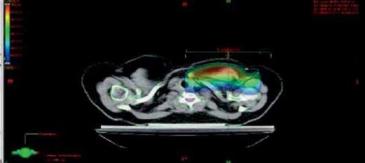

- Podle rozměrů pacientky volit vyšší energii X záření pro

tangenciální pole (u velké vzdálenosti mezi CP tangenciálních poli

22 cm a více) nebo i u axillárního pole (příliš hluboké PTV): např.

6X + 18X nebo 6X + 6X technika pole v poli nebo 18 X (zvážit

použití bolusu). (obr. 3a, b, c, obr. 4a, b).

Obr. 3a optimalizace RT axila: 1 přední pole X záření en. 6 MV

Obr. 3b optimalizace RT axila: 1 přední pole X záření en. 18 MV

Obr. 3c optimalizace RT axila: přední pole X záření en. 6 MV + 18 MV

Obr. 3d optimalizace RT axila: 2 kontra pole X záření en. 6MV